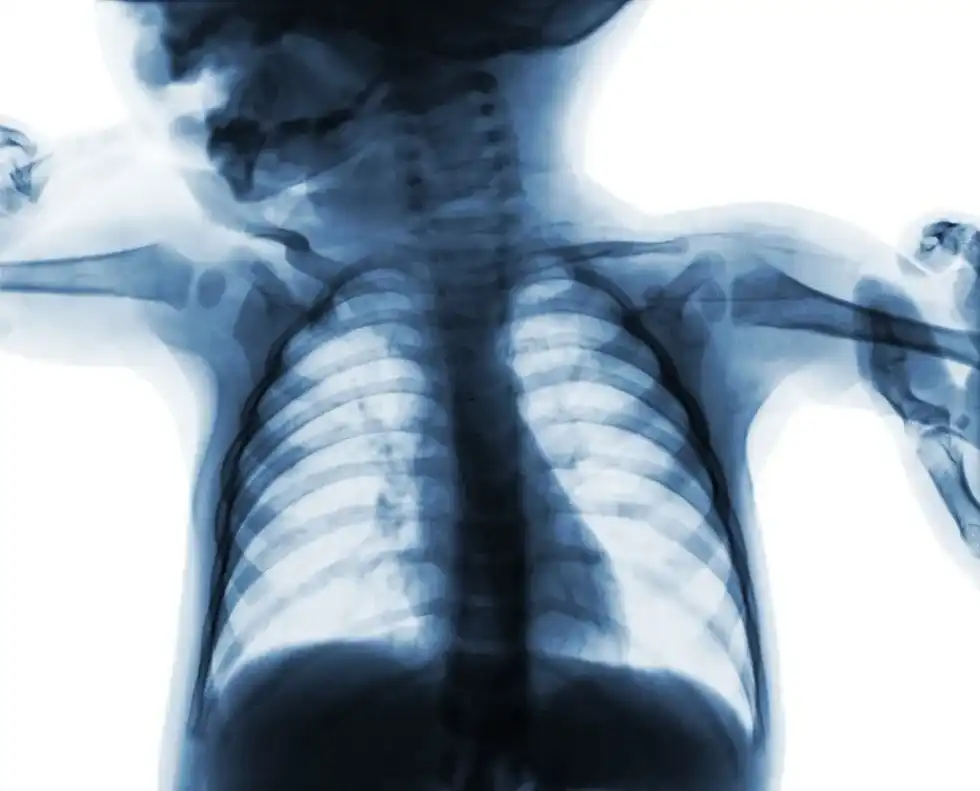

An x-ray scan for babies takes a fraction of a second. The image is recorded either onto photographic film or, more commonly these days, digitally.

The medical x-ray is among the most versatile and important tools for a doctor to discover what's wrong with a child. Most famously, an x-ray can quickly reveal broken or damaged bones on almost any part of the body.

Jaw x-rays are a routine part of many visits to the dentist. A chest x-ray can pick up conditions as diverse as pneumonia, tumors, damaged blood vessels and any objects that may have been swallowed or inhaled.

X-rays are an exceptionally good tool for diagnosis, helping a doctor to understand why your child might be breathing with difficulty or constantly coughing.